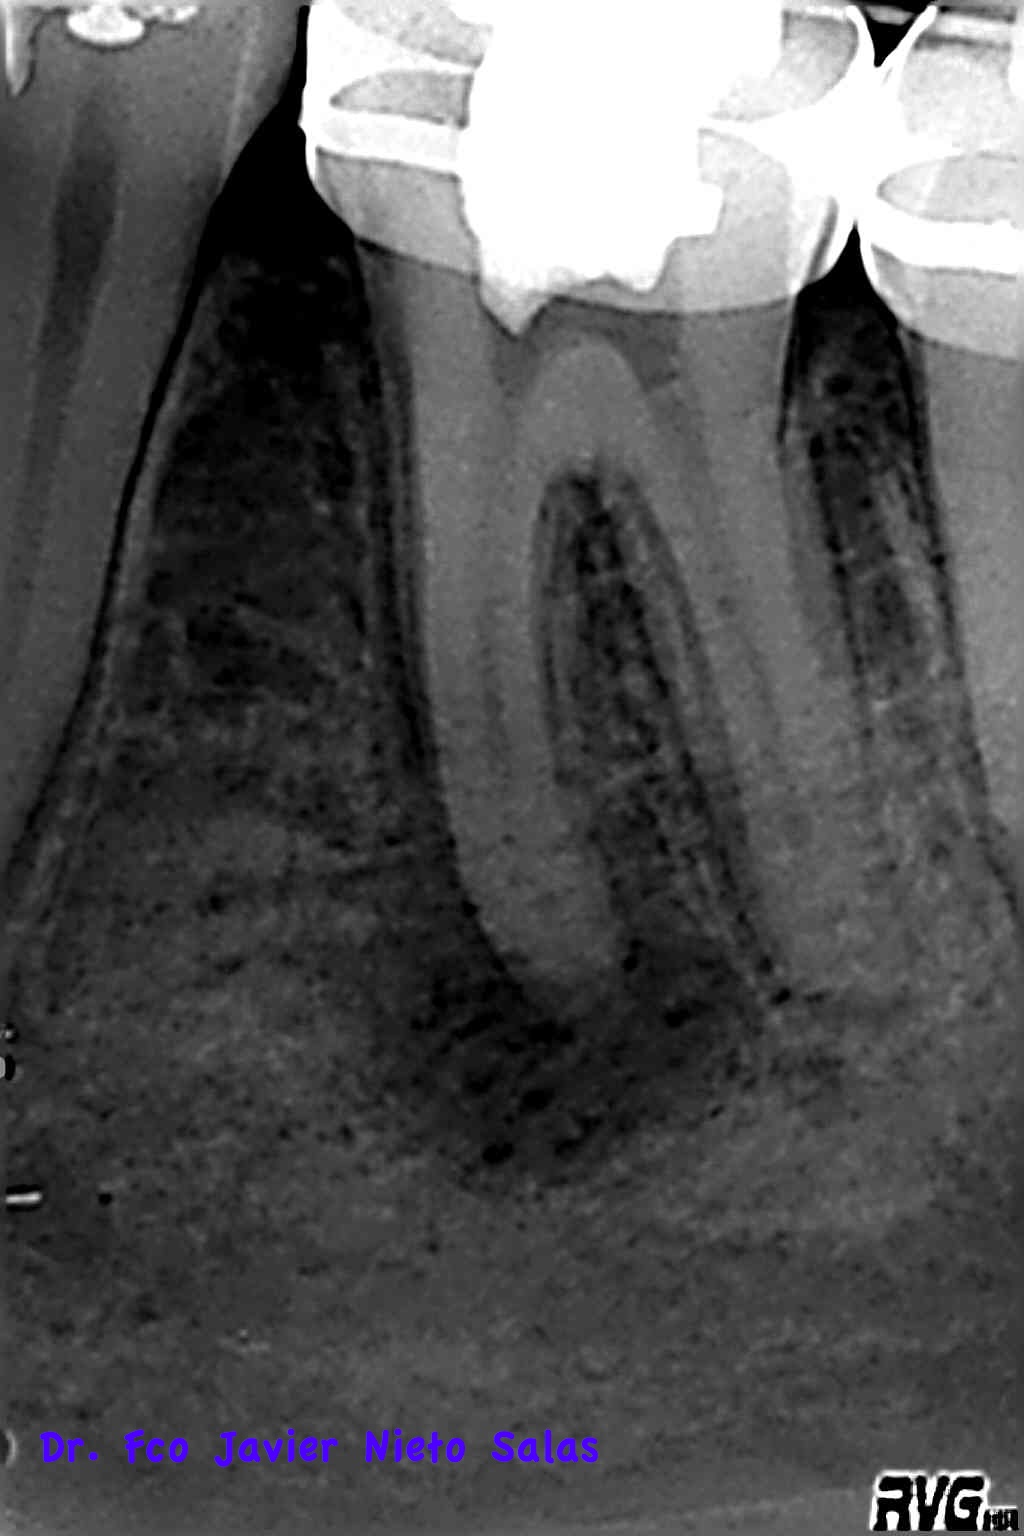

La paciente llegaba a la consulta con bandas de ortodoncia:

Presentaba una lesión periapical crónica, su diagnóstico es una necrosis pulpar con periodontitis apical crónica.